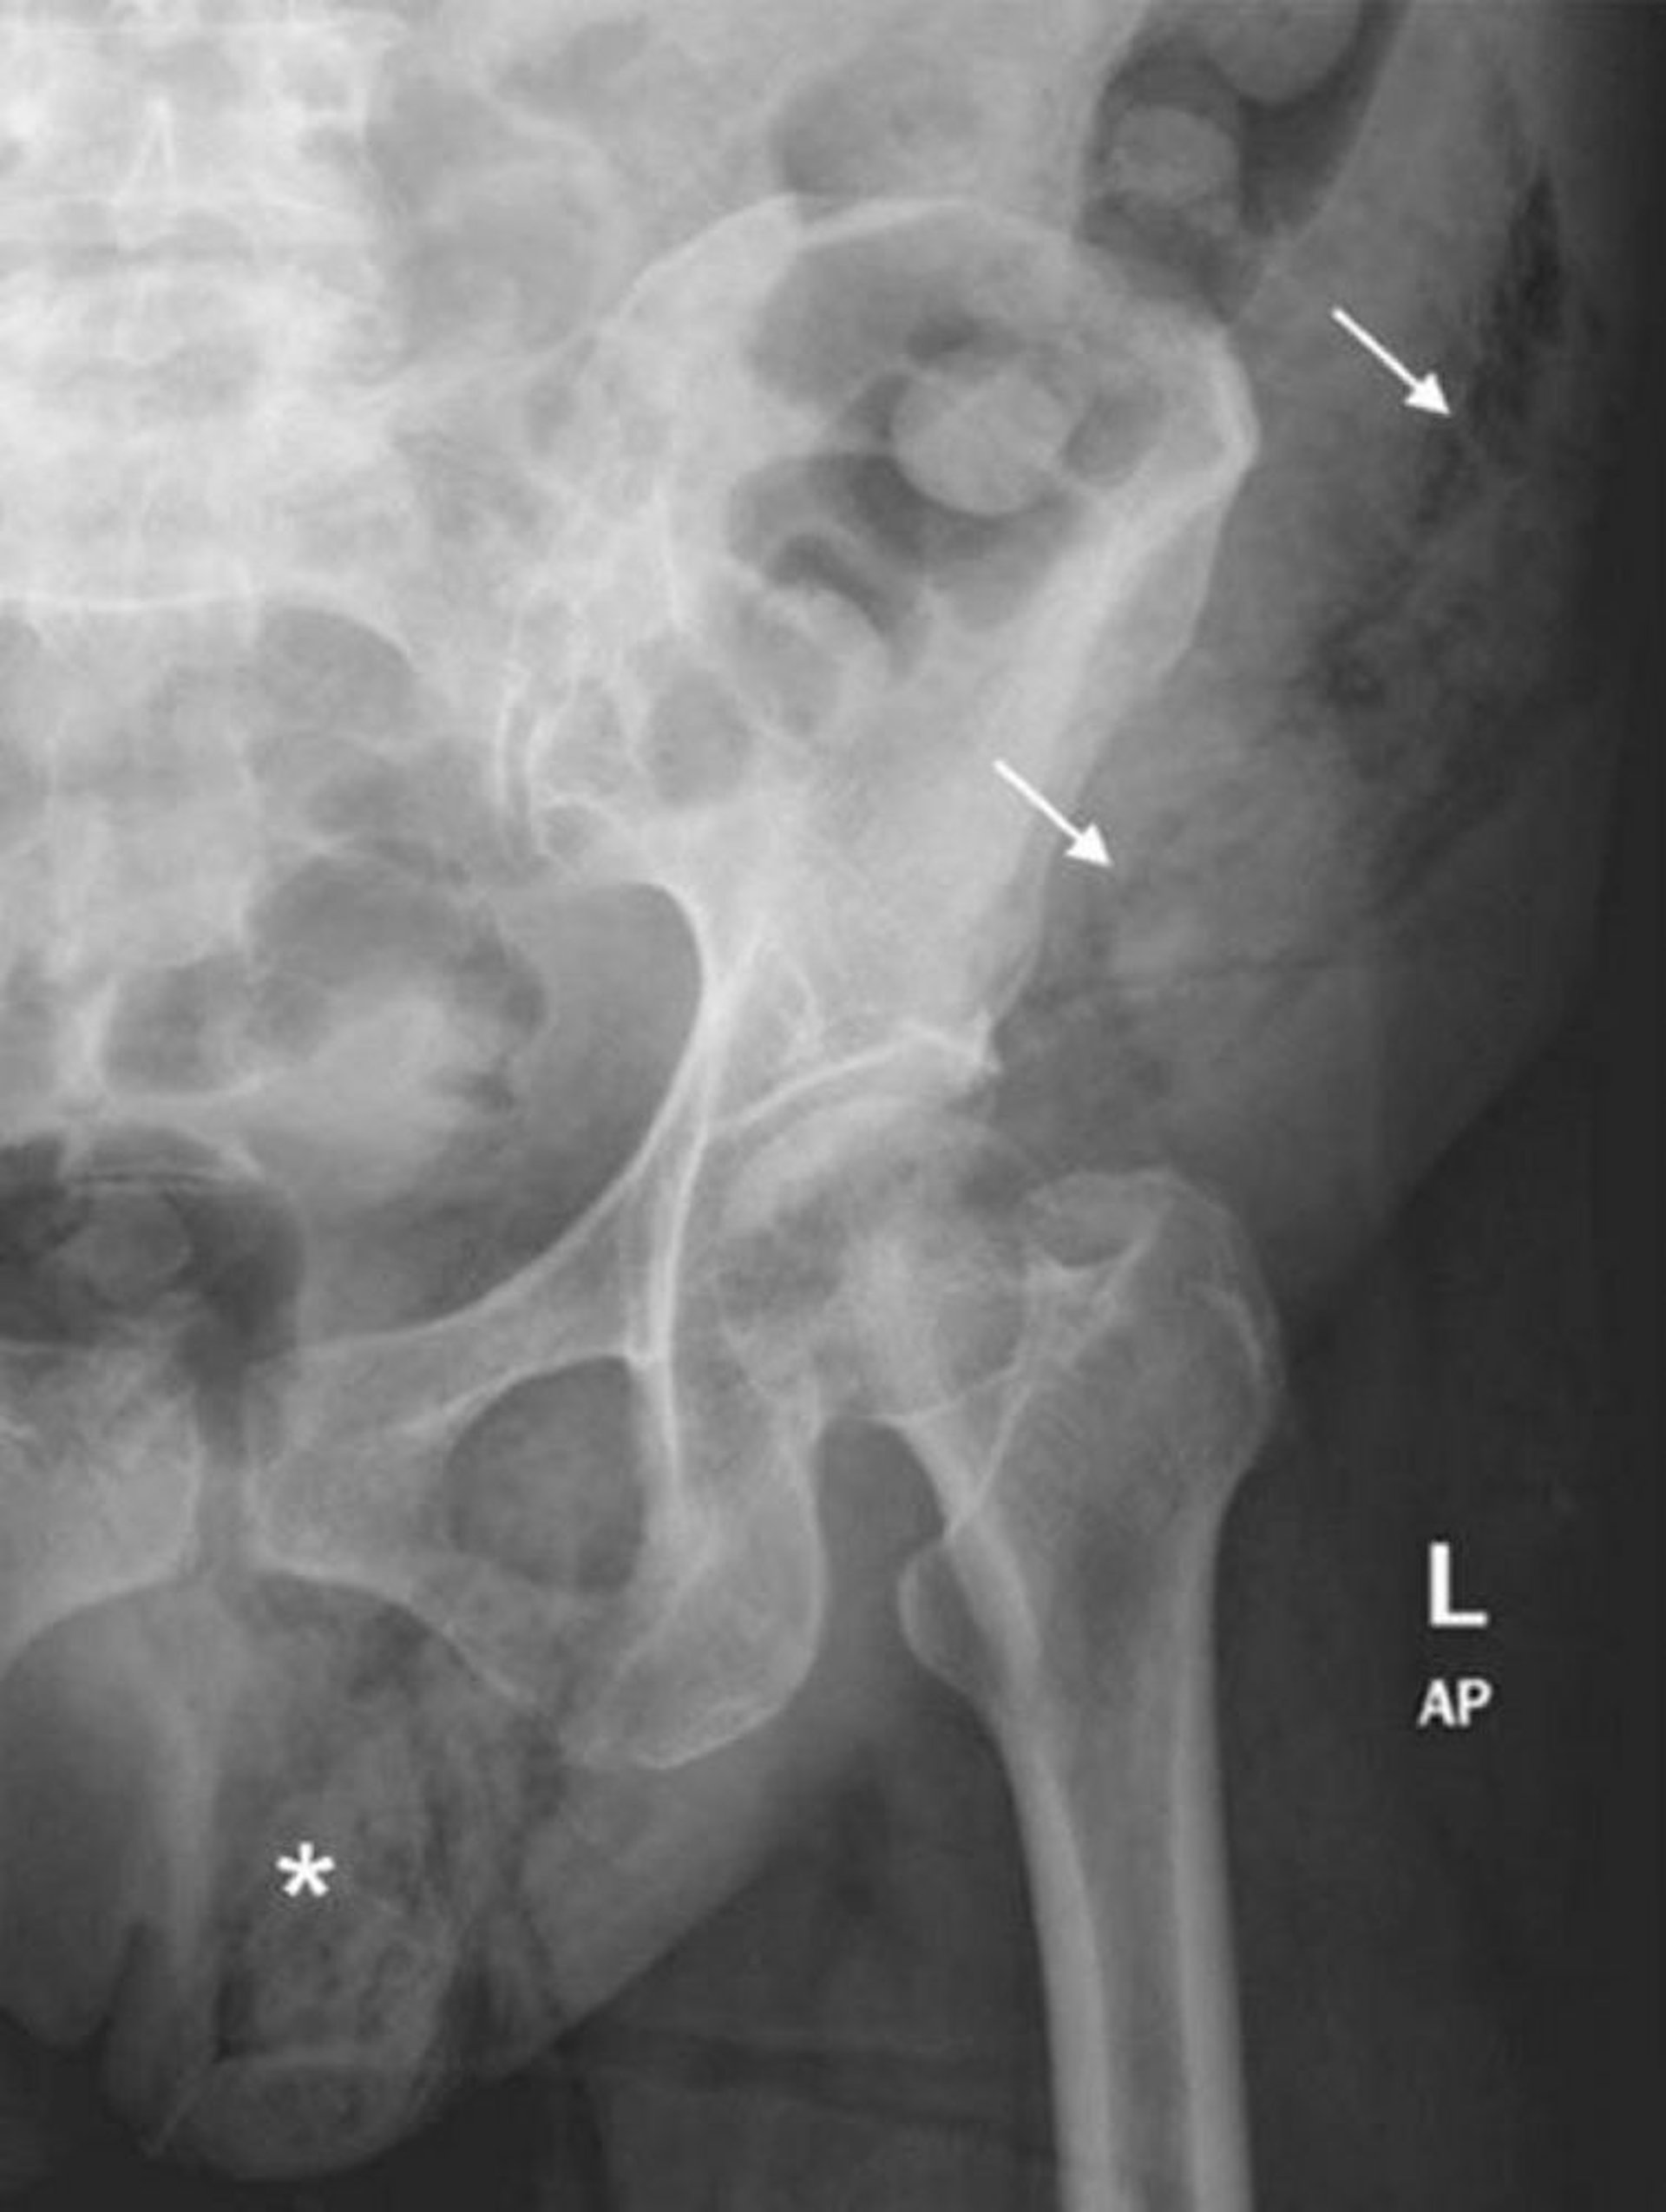

Gangrena de Fournier (Radiografía abdominal)

Esta radiografía abdominal muestra una extensión de gas en los tejidos blandos desde el hemiscroto izquierdo (*) hasta la pared abdominal izquierda (flechas).